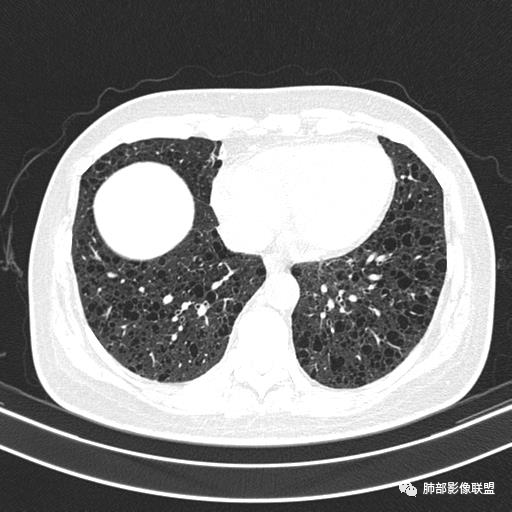

中年女性,不吸烟

双肺弥漫囊腔,累及肋膈角,囊腔形态相对规则单一。

CT平扫示双肺弥漫分布大小不等囊状薄壁透光区,无内、中、外带分布差异,间质稍示增厚。拟LAM

中年女性育龄期妇女,咳嗽气喘,无吸烟史,有苯吸入史。影像:双肺弥漫均匀小囊腔,无明显分布优势,囊腔形态欠规则,壁薄,部分囊腔边缘血管征,伴双肺弥漫磨玻璃影,无结节,考虑lam,鉴别苯中毒肺损伤,囊腔多有分布优势,小叶中心分布为主,形态规整等

女,46,活动性气喘1年。苯吸入史半年。胸部CT:两肺弥漫囊腔,上至肺尖,下至肋膈角,形态类似小囊腔。考虑:LAM,鉴别LIP,BHD,PLCH等。

双肺弥漫大小不一薄壁含气囊腔,囊间肺组织正常,正常肺背景,肺尖肺底受累;青年女性,气喘,支持LAM

双肺多发大小相近的囊状影,分布趋势趋于一致,中年女性,考虑LAM。部分囊内见血管及分隔影,小叶中心性肺气肿代排

CT表现:双肺弥漫大小不等的薄壁囊腔,囊壁<2mm,外形规则,血管影多位于囊腔周围,囊腔之间肺组织正常,随着疾病进展到晚期,囊腔变大、增多,不可胜数,囊腔可融合成较大的囊,与肺气肿相似,形成间质性肺纤维化。部分病例可出现结节影。